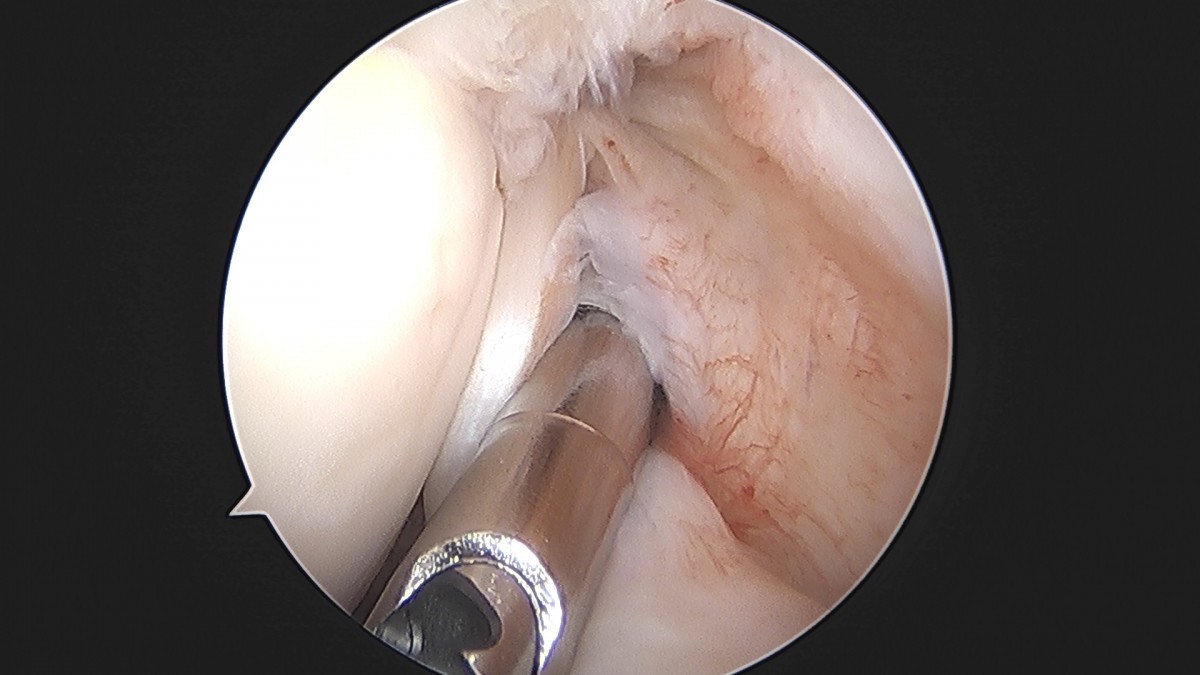

이재상원장님 어깨 견봉하 감압술 및 관절낭 이완술 주혜O 환자

dae765e4d9ac96aee867c9d6292d8784_1758003913_4176.jpg